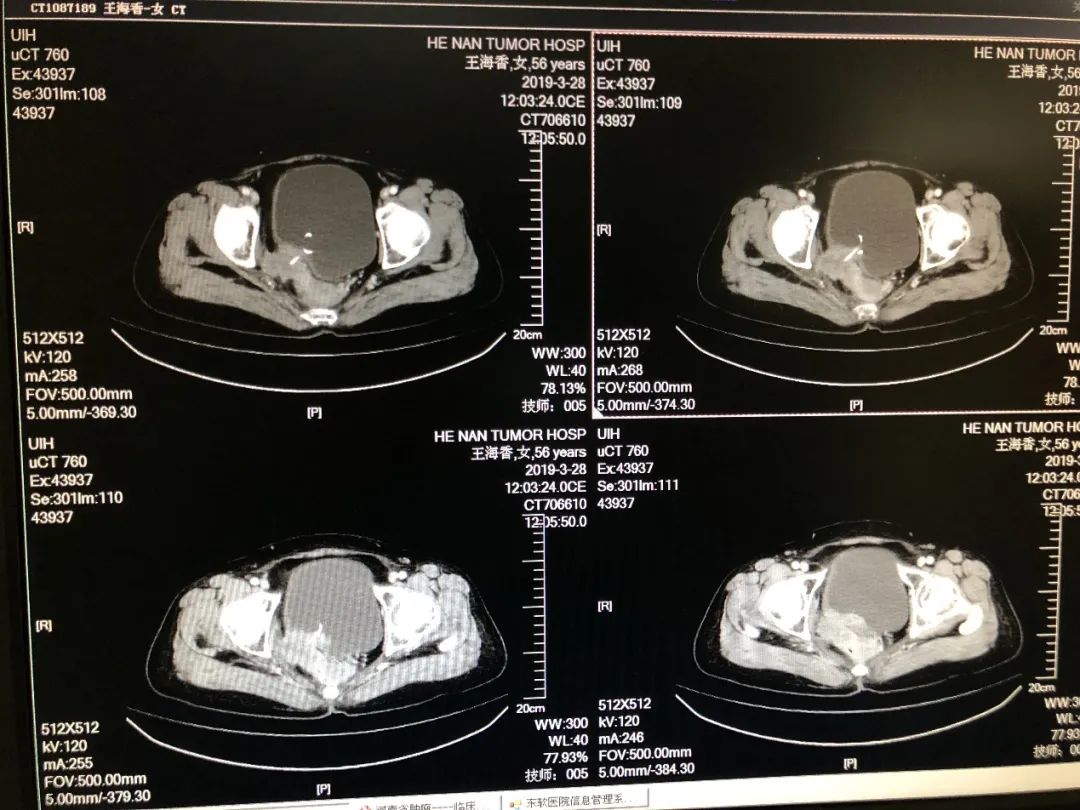

今天做了一台直肠癌术后放疗后复发患者,切除了全膀胱,全子宫,做了输尿管乳头成型。手术注意事项及体会分享给大家!

1.术前一定要了解该手术后可能出现的并发症。术前影像显示,右侧盆壁受侵,该类手术后可能出现右侧下肢运动感觉功能障碍及疼痛,一定要反复强调。

图片